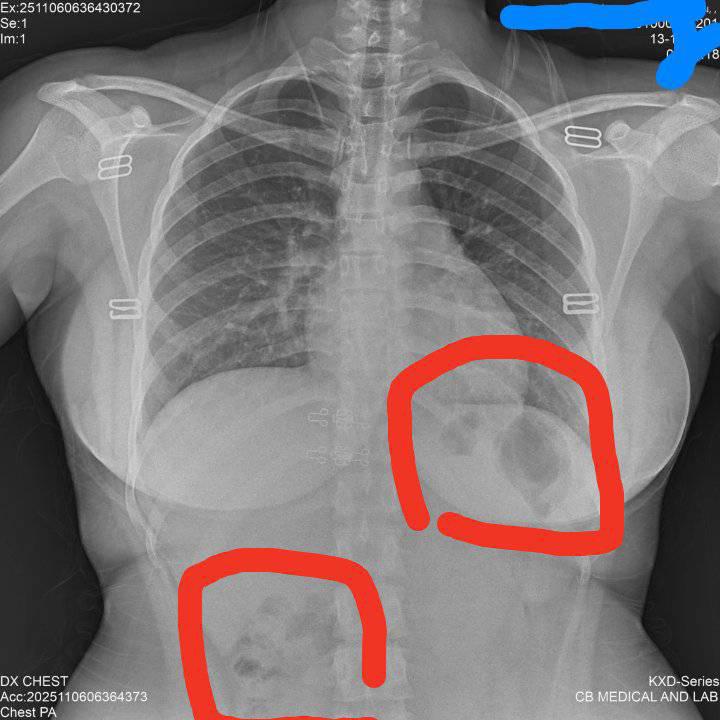

ตรวจสุขภาพแล้วทางโรงพยาบาลส่งผลตรวจมา มีภาพx-rayด้วย วงสีแดงในภาพคืออะไรคะ แต่ในข้อมูลบอกว่าปกติทุกอย่าง